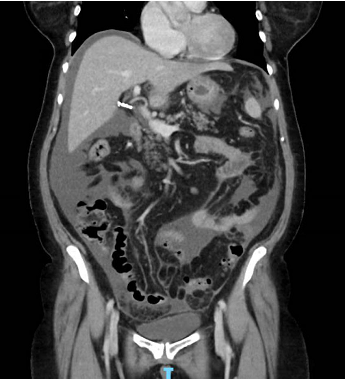

In hospital the patient was extensively investigated for a unifying diagnosis to account for her presentation. Cardiac, hepatic, and renal failure as causes for ascites were ruled out through normal biochemistry (including brain natriuretic peptide level), and imaging including an abdominal ultrasound confirming a normal liver contour and no secondary signs of chronic liver disease or portal hypertension. Of initial interest, the tumour marker cancer antigen 125 was elevated at 476units/mL (normal range <35), however a pelvic ultrasound was normal, with gynaecology opinion outlining that an ovarian malignancy as the underlying cause for presentation was unlikely. For completeness, a sexually transmitted infection screen was inconsistent with pelvic inflammatory disease. Given no diagnosis had been made, two separate paracentesis procedures to capture fluid for analysis were performed. The serum-ascites albumin gradient on both was <1.1g/L suggesting an exudative pathology such as infection or malignancy. Despite this, multiple fluid cultures, including assessment for tuberculosis, and both cytological assessments were normal. A repeat CT, now including the chest, again demonstrated only ascites with no evidence of infection, lymphadenopathy or malignancy in either the abdominal or thoracic cavities (Figure 2).

Figure 2 Coronal slice of repeat CT chest/abdomen/pelvis with ongoing ascites and peritoneal stranding, however no other signs of infection or malignancy.